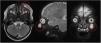

Al mes de la ecografía y debido a un crecimiento progresivo y a la pérdida de movilidad de la lesión, se solicita una RMN (fig. 1).